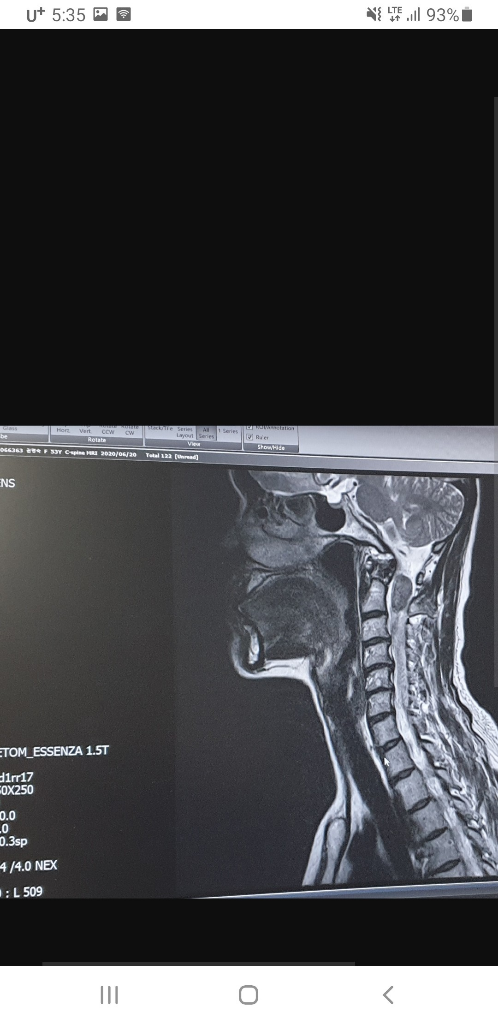

목쪽에 있는 양성종양을 제거한지 3년정도 됐는데요.

대학병원에서 수술받은지 3년정도 지났는데 mri를 다시 찍어보는게 좋을까요? 가끔씩 머리가 아프다고 말씀드렸더니 휴유증이라고 하시던데 괜찮을까요?

• 1번 째 사진